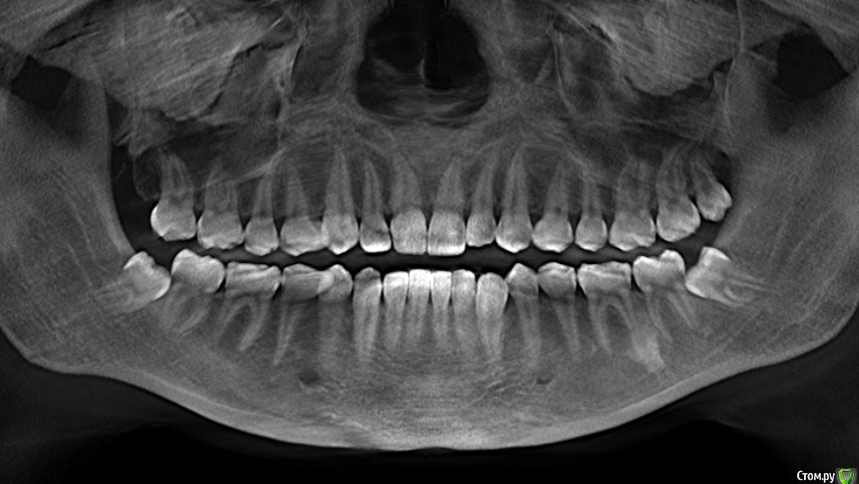

juliavesna Опубликовано 28 июня, 2017 Поделиться Опубликовано 28 июня, 2017 (изменено) Здравствуйте! В прошлом году при рассмотрении вариантов ортодонтического лечения обнаружили 2 нижних ретивированных зуба мудрости и один верхний обычный. Практически сразу удалили один нижний - с левой стороны (на снимке правый соответственно) и после этого через неделю у стоматолога при лечении одного из зубов, выявила трудности с закрыванием рта. В связи с переездом удаление второго ретинированного зуба отсрочилось. Меня он не беспокоит, точно так же как в принципе ничего на протяжении почти года после удаления не беспокоило.Недавно я записалась на удаление второго нижнего зуба через 2 недели, но по какой-то причине состояние суставов резко усугубилось буквально несколько дней назад. На протяжении нескольких дней чувствовала конкретные заклинивания при зевании например или при визите к стоматологу, движение челюсти неровное, как будто что-то смещается, иногда было даже при открывании рта до среднего уровня. Сегодня добавилась ноюще-давящая боль в области лица и ощущение слабости при жевании. Когда точно начались проблемы с суставами я не могу сказать, возможно где-то иногда и чувствовала какой-то дискомфорт, но меня это не беспокоило и внимания я не обращала. Такого как сейчас не было никогда.Вопрос заключается в том, что сейчас делать и с чего начинать. Насколько необходимо сейчас удаление зуба? Могло ли наличие зубов мудрости или наоборот удаление одного из них спровоцировать проблемы с суставами? Изменено 28 июня, 2017 пользователем juliavesna Ссылка на комментарий

juliavesna Опубликовано 5 июля, 2017 Автор Поделиться Опубликовано 5 июля, 2017 Так как сустав сейчас беспокоит главным образом с левой стороны, возник вопрос, может ли это провоцировать верхняя восьмерка? Или нереально? (нижняя с левой стороны уже удалена). Пытаюсь разобраться, почему могли возникнуть проблемы с суставами. Ортодонты говорят, что с прикусом значительных проблем нет, которые могли бы сыграть в этом роль, да и начала чувствовать суставы сравнительно не так давно. Ссылка на комментарий